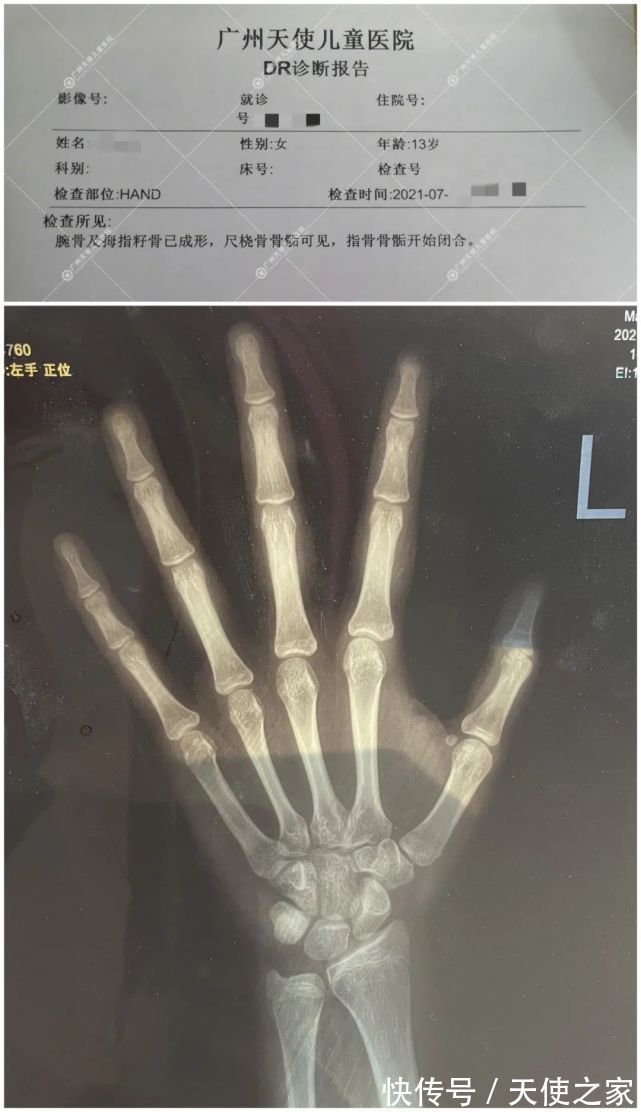

于是妈妈在网上查到各种长高方法,偶然发现广州天使儿童医院有一位医生在治疗矮小症方面较专业权威,妈妈带着小钰于2021年7月28日来院由武翠凡主任接诊。武主任了解到小钰的过往病史,针对小钰的生长发育情况来看,为其做了科学的检查:骨龄测评、微量元素、血常规、生长激素激发试验等检查。

报告显示:小钰腕骨及拇指籽骨已成型,尺桡骨骨骺可见,指骨骨骺开始闭合。小钰体内生长激素分泌不足,缺乏生长激素,骨龄偏大,导致身高矮小。妈妈了解情况后,问主任还有没有办法可以让孩子长高,通过武主任的耐心解释及分析,给出治疗方案,由于小钰体内缺乏生长激素,采取替代疗法加中医药物治疗及中药膏贴,有利于小钰体内生长激素的补给和身心脾胃的调理及结合运动饮食作息,促进生长发育,助于长高。